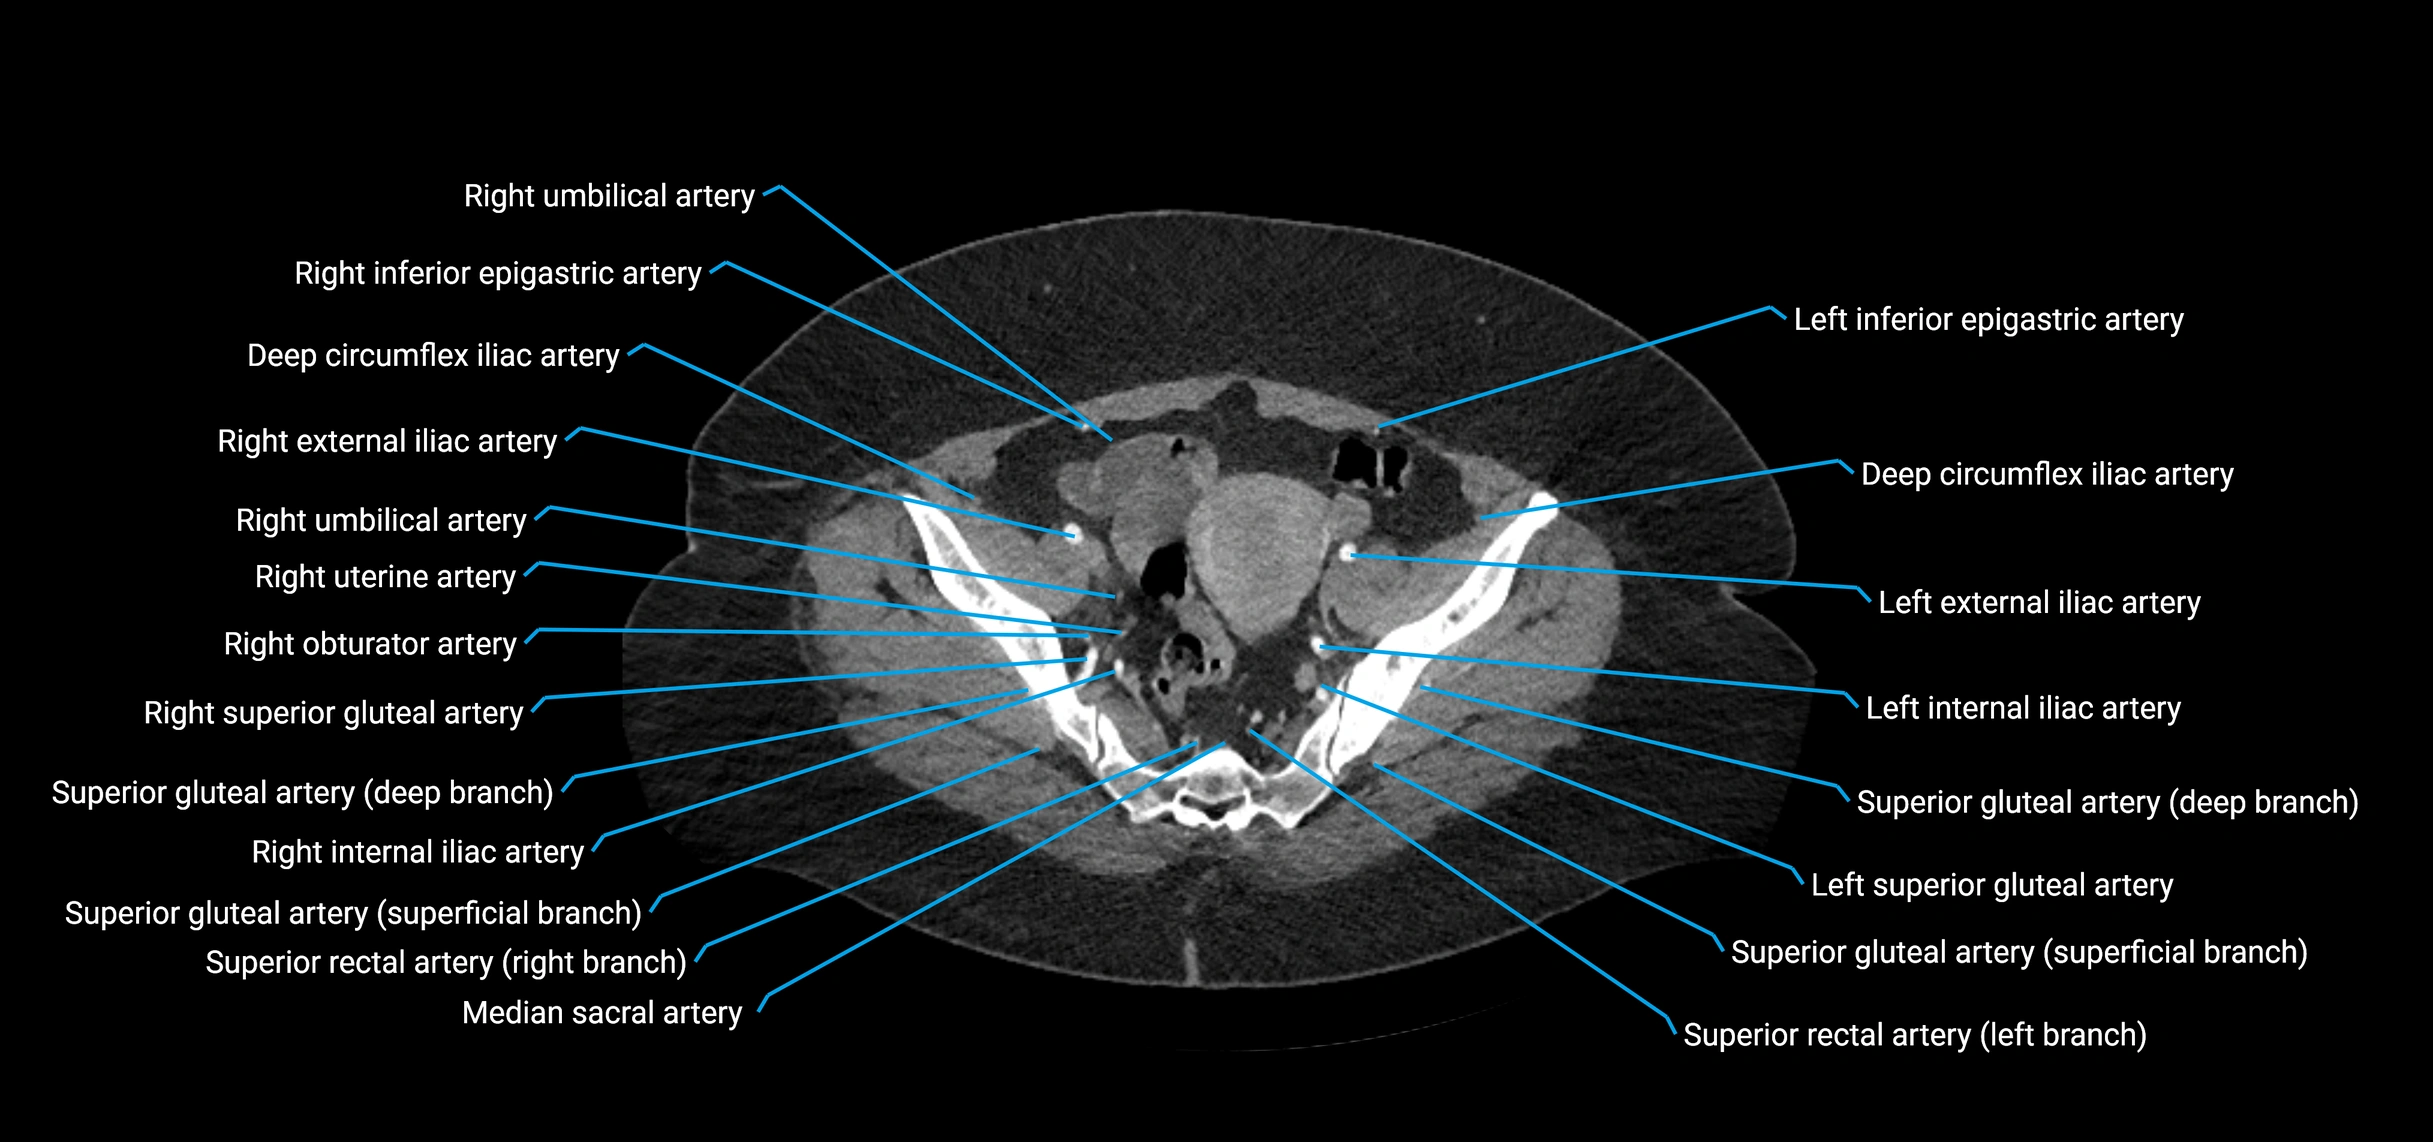

CT images

image

Contrast-enhanced CT (CTA):

• Gold standard for abdominal aortic imaging

• Provides excellent detail of lumen, wall, aneurysm, thrombus, and branch vessels

• Multiplanar and 3D reconstructions help in aneurysm measurement, stent graft planning, and dissection evaluation

• Terminal branches: right and left common iliac arteries